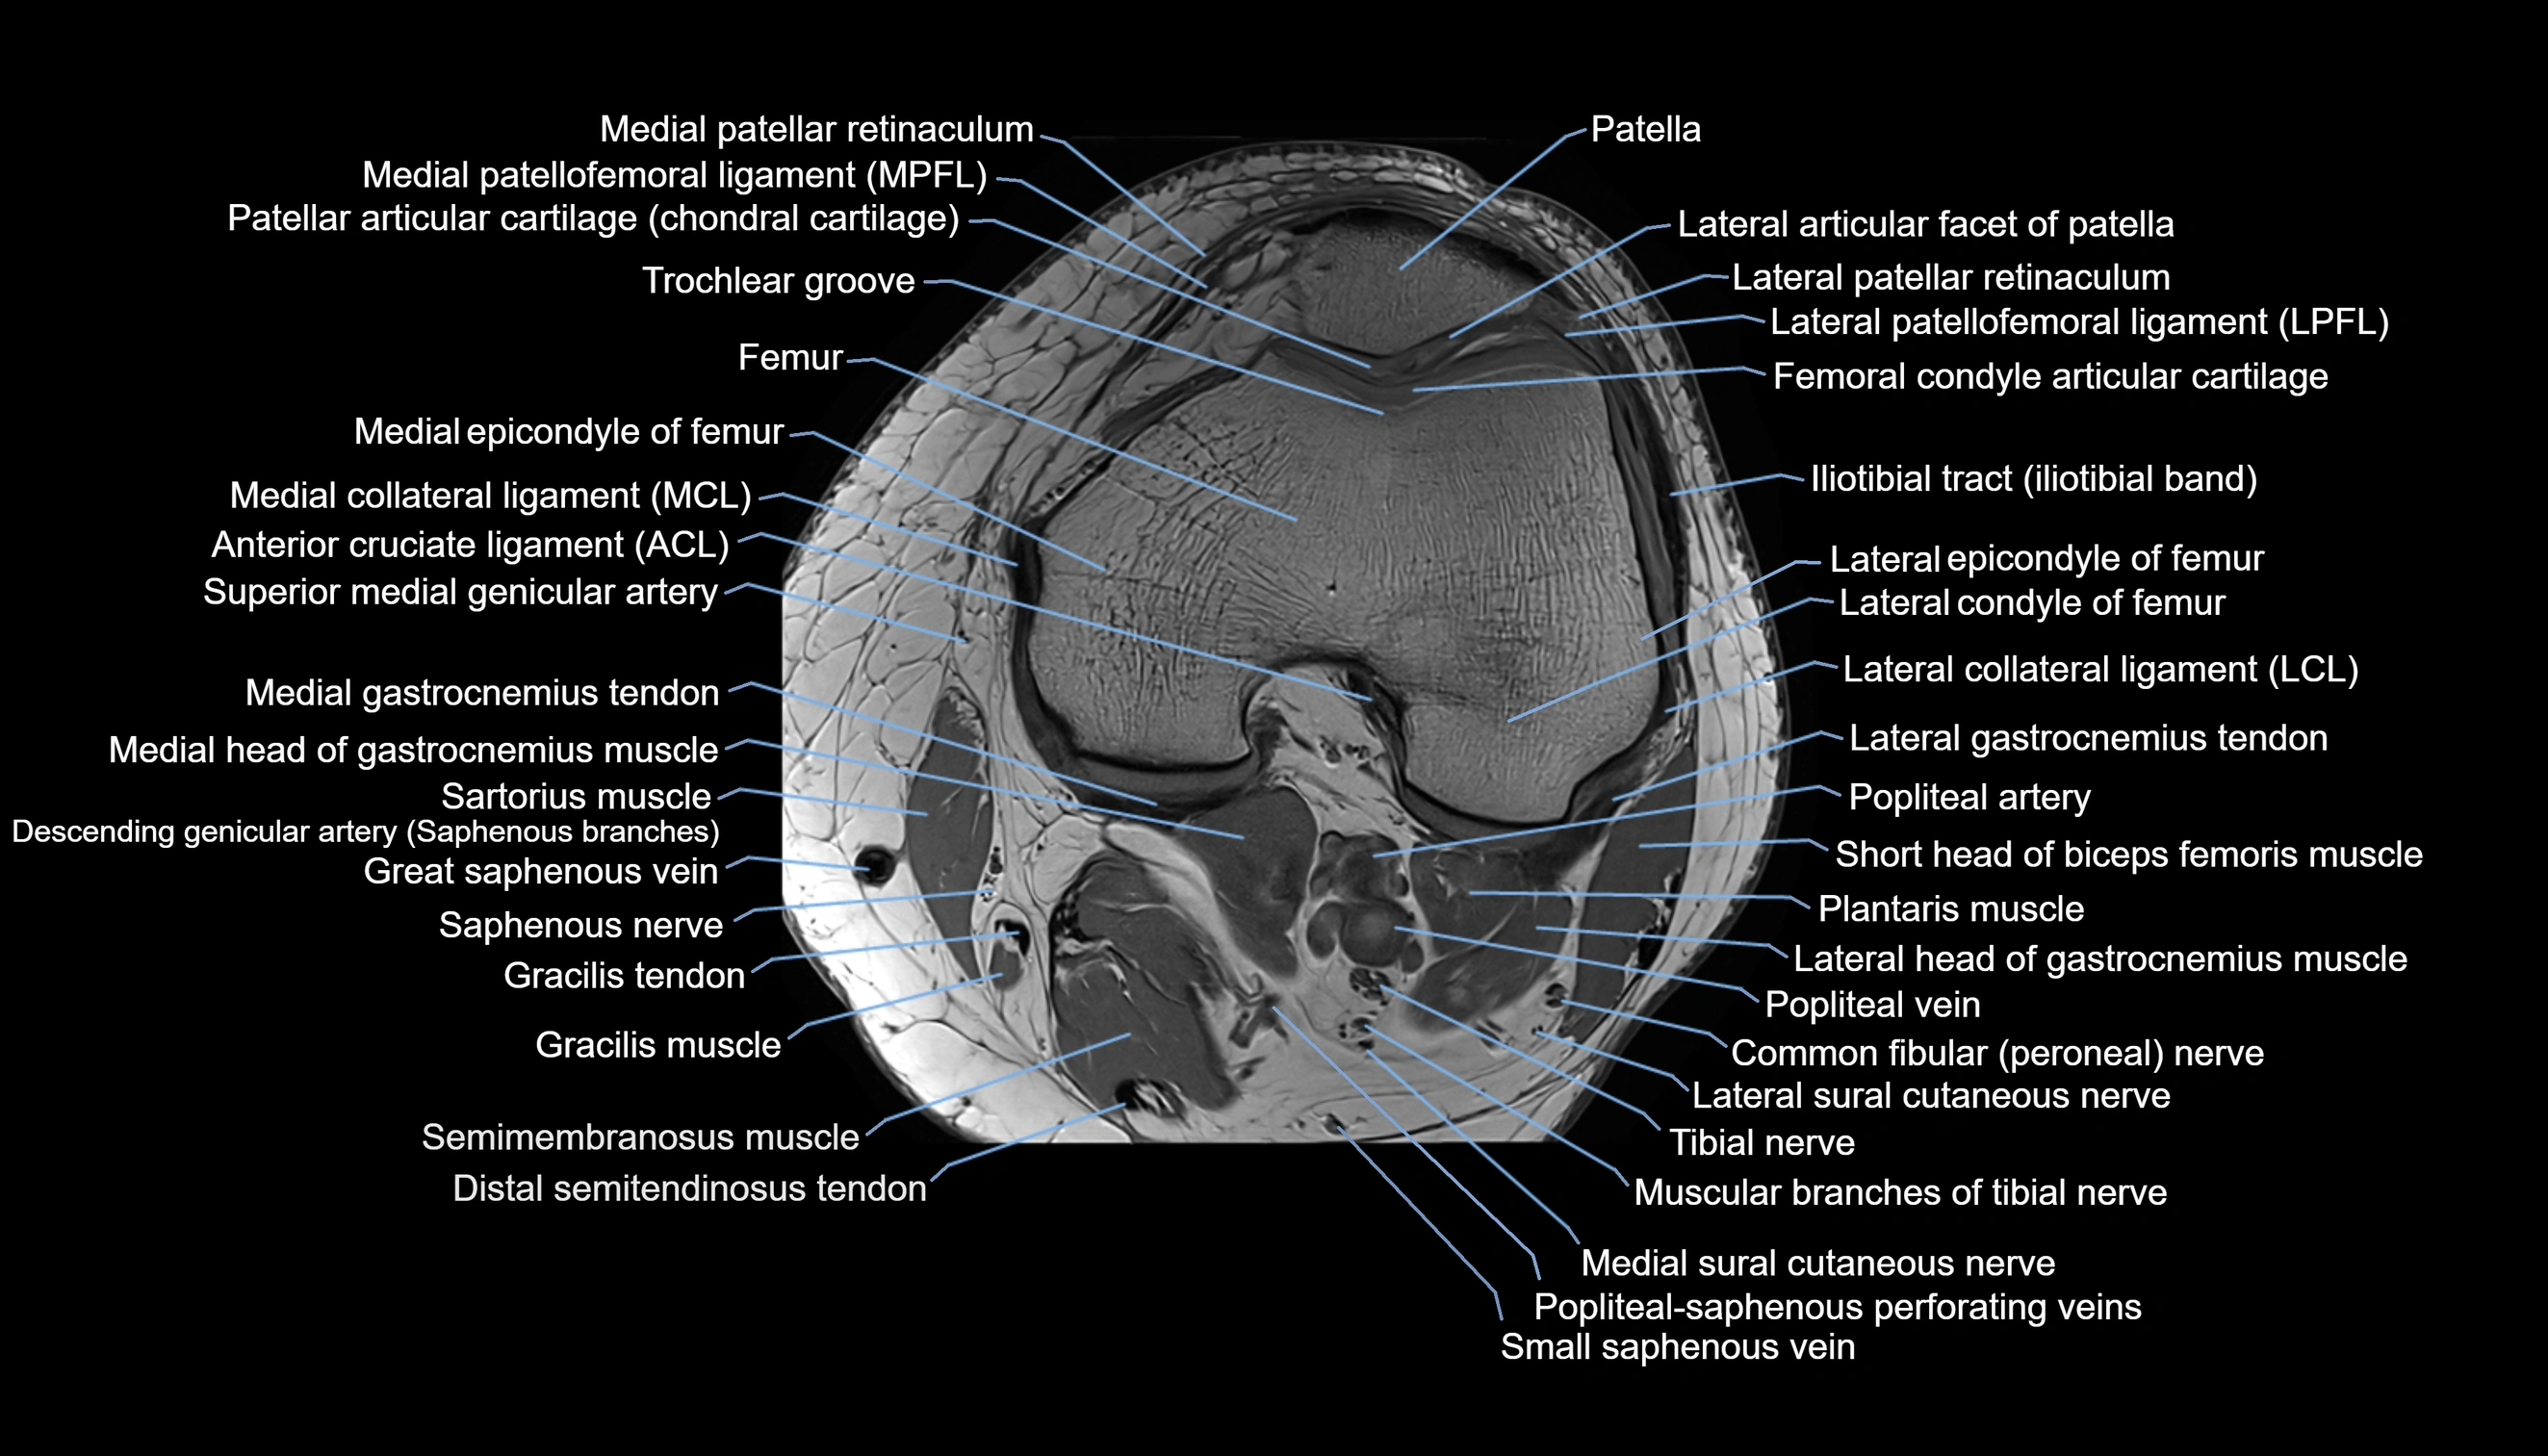

- Anterior cruciate ligament

- Femoral condyle articular cartilage

- Lateral articular facet of patella

- Lateral collateral ligament

- Lateral condyle of femur

- Lateral epicondyle of femur

- Lateral gastrocnemius tendon

- Lateral head of gastrocnemius muscle

- Lateral patellar retinaculum

- Lateral patellofemoral ligament

- Lateral sural cutaneous nerve

- Medial collateral ligament

- Medial condyle of femur

- Medial epicondyle of femur

- Medial gastrocnemius tendon

- Medial head of gastrocnemius muscle

- Medial patellar retinaculum

- Medial patellofemoral ligament

- Medial sural cutaneous nerve

- Muscular branches of tibial nerve

- Patella

- Patellar articular cartilage

- Popliteal artery

- Popliteal lymph nodes

- Popliteal vein

- Popliteal–Saphenous perforating veins

- Posterior cruciate ligament

- Sartorius muscle

- Small saphenous vein

- Superior lateral genicular vein

- Superior medial genicular artery

- Tibial nerve

- Trochlear groove

- Vastus lateralis muscle

- Vastus medialis muscle

- great saphenous vein